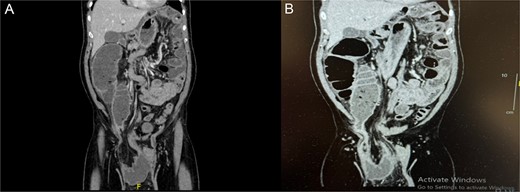

The patient was admitted for further investigations. Basic routine laboratory tests were unremarkable except for mildly elevated creatinine levels, likely due to dehydration secondary to vomiting and diarrhea. A computed tomography (CT) was ordered due to diagnostic uncertainty given some of the patient’s family members recently suffered from gastroenteritis or if his symptoms were caused by the hernia. The CT scan demonstrated a dilated bowel segment originating from the afferent loop of the TC, which was herniated into the hernia sac and collapsing again at the terminal ileum. The isolated segment showed significant dilation, with a maximum diameter of 6.7 cm. Bowel segments both proximal and distal to this affected segment appeared collapsed, highlighting the transition zone and free fluid was found in the hernia sac and the peri-splenic area (Fig. 1).

(A, B) Coronal abdominal CT showing right side inguino-scrotal hernia that contains mesenteric fat and vessels with long segment of transverse colonic loop, there is proximal dilatation of the right side of the colon reaching a competent ileo-cecal valve and not associated with dilatation of the small bowel loops. The left side colon is collapsed.